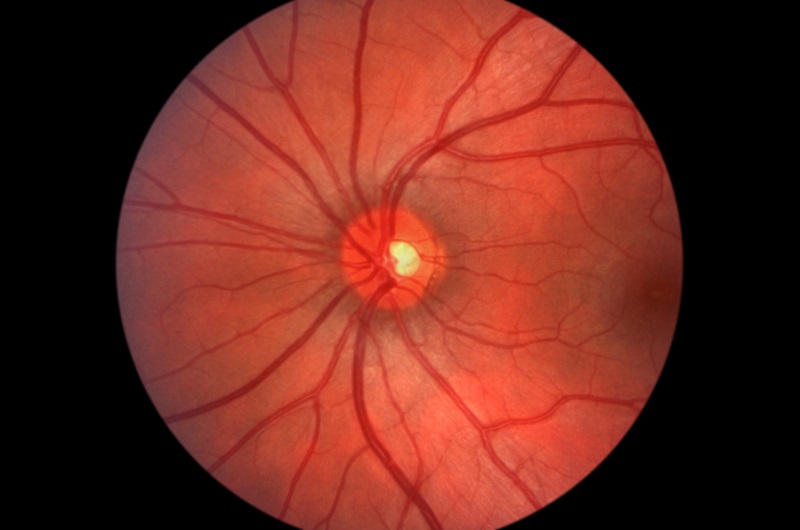

Glaucoma occurs from damage to the eye’s optic nerve and can often lead to loss of vision and blindness. To detect glaucoma, our highly trained doctors will perform a proper screening to determine severity, examine the damage, and help you manage your glaucoma.

Early detection of glaucoma is crucial in preventing vision loss and blindness; the earlier the better. However, there is no official cure for glaucoma. There are several treatment methods that manage, slow down, or halt the process. Treatment for glaucoma will vary depending on the stage and severity for each individual patient.

Macular degeneration is a deterioration of the central portion of the retina, the inside layer of the eye that records the images we see and sends them through the optic nerve from the eye to the brain for processing. The macula, or the center of the retina, is responsible for focusing central vision in the eye and controls our ability to see and process information.